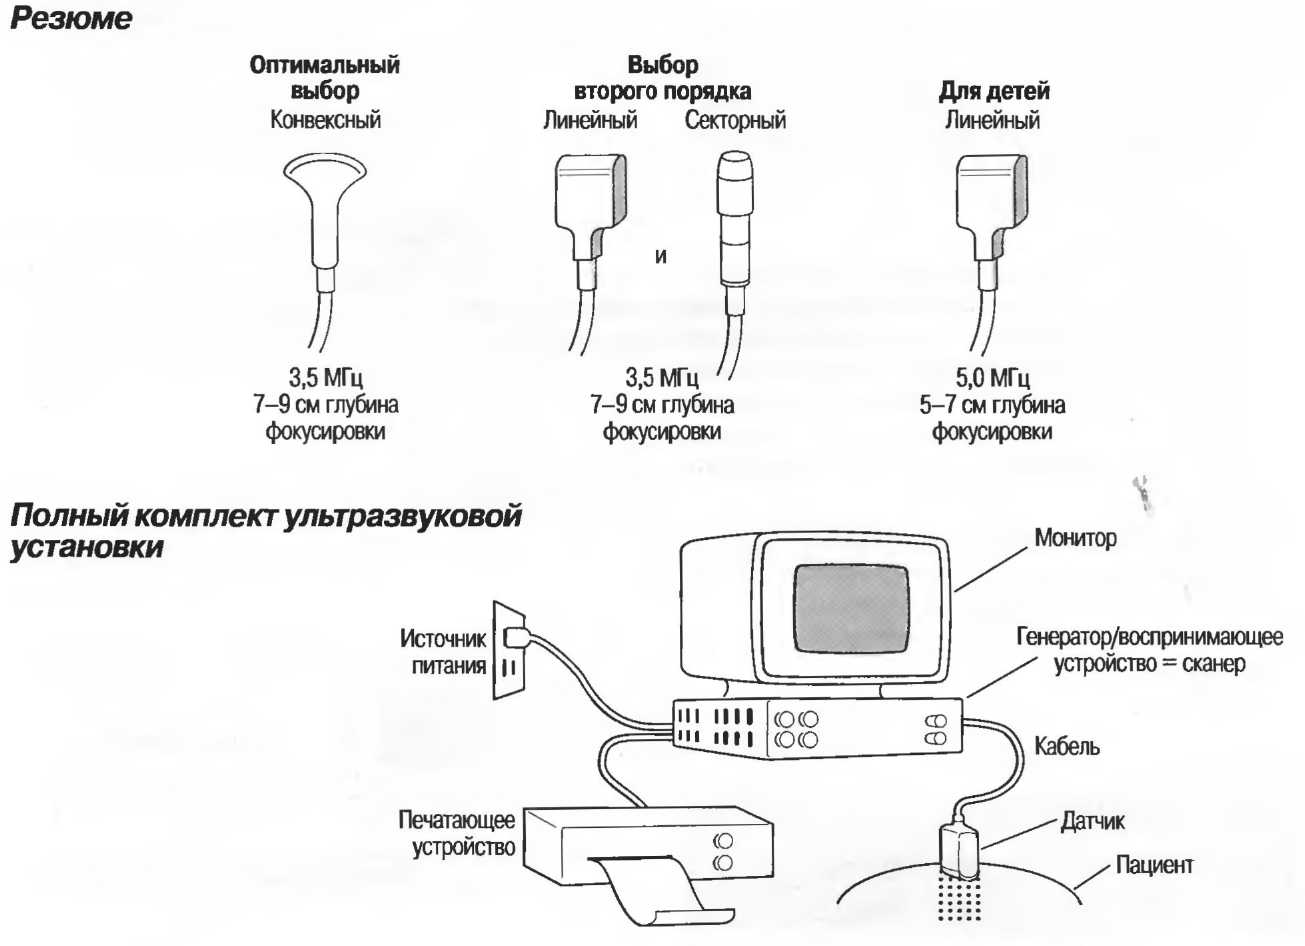

Выбор ультразвукового сканера

Монитор

Сканер

Обслуживание сканера

Контрольные устройства сканера

Регистрация изображения

Выбор соответствующего датчика

Оборудование кабинета ультразвуковой диагностики

Какие необходимы электрические розетки?

Когда сканер доставлен

Выбирайте сканер для тех исследований, которые необходимы в условиях Вашего госпиталя; нет необходимости покупать оборудование и дополнительные устройства, которые точно не будут часто использоваться. Сканер должен покрайней мере соответствовать спецификации, приведенной в приложении (с. 321). Кроме технических характеристик аппарата, необходимо придерживаться некоторых общих правил при выборе аппарата.

Монитор

Монитор (телевизионный экран) должен иметь размеры не менее 13x10 см (примерно 16 см по диагонали).

Сканер

1. Сканер должен быть портативным и достаточно легким для переноски хотя бы на 100 м.

2. Сканер должен быть пригоден для использования в условиях местного климата, т.е. должен быть защищен от пыли и пригоден для использования, при необходимости, в условиях низкой или высокой температуры.

3. Сканер должен быть достаточно прочным для любых условий транспортировки и хранения. Он не должен повреждаться при перевозке воздушным транспортом или в машине по плохим дорогам.

4. Сканер должен удовлетворительно работать от источников энергии в госпитале или клинике, в которых планируется его установка. Эти характеристики необходимо проверить и еще раз проверить, прежде чем будет получен аппарат. Установка должна быть совместимой с местным напряжением и частотой тока и должна выдерживать колебания напряжения в местной сети.

Обслуживание сканера

Для обслуживания сканера необходимо определенное пространство. Оно должно быть достаточным для установки прибора данного вида таким образом, чтобы можно было проводить проверку оборудования и замену запасных частей.

Контрольные устройства сканера

Сканер должен быть оборудован видеомонитором (телевизионным экраном), а для контроля качества изображения необходимо наличие:

1. Устройства регулировки общей чувствительности для изменения количества общей информации с видеоэкрана.

2. Устройства компенсации затухания ультразвука в поверхностных (близкорасположенных) и глубокорасположенных (отдаленных) структурах. Эти устройства называются устройствами регулировки чувствительности по глубине.

3. Устройства «замораживания» изображения для фиксации изображения на экране в течение необходимого времени.

Функции измерения, которое должно производиться электронным способом и обычно производится помещением маленьких маркеров — точек по обе стороны измеряемого расстояния. Значение расстояния автоматически высвечивается на экране в сантиметрах или миллиметрах. В акушерстве используются специальные биометрические таблицы.

Выбор соответствующего датчика

Наилучшим датчиком для общей практики является конвексный датчик с частотой 3,5 МГц с фокусировкой на расстоянии 7-9 см. Если такого датчика нет, необходимо наличие линейного секторного датчика с частотой 3,5 МГц. При необходимости исследования детей и худых взрослых желательно дополнить набор датчиком с частотой 5 МГц с фокусировкой 5-7 см.

1. Ультразвуковые исследования в акушерстве. Для общих исследований в акушерстве используется линейный или конвексный датчик с частотой 3,5 или 5 МГц с глубиной фокусировки на 7-9 см. Если закупается только один датчик, выбирайте датчик с частотой 3,5 МГц. Датчик с частотой 5 МГц предпочтителен на ранних сроках беременности. В поздние сроки беременности лучше использовать датчик с частотой 3,5 МГц.

2. Ультразвуковые исследования в общей практике. Если проводятся исследования в верхней части живота и таза у взрослых, в том числе и акушерские исследования, предпочтительнее выбор секторного или конвексного датчиков с частотой 3,5 МГц с глубиной фокусировки на 7-9 см.

3. Ультразвуковые исследования в педиатрии. Для детей необходим датчик с частотой 5 МГц с глубиной фокусировки на 5-7 см. При исследовании мозга новорожденного используется секторный датчик с частотой 7,5 МГц с глубиной фокусировки на 4-5 см (этот датчик также используется для исследования яичек и структур шеи у взрослых).

Оборудование кабинета ультразвуковой диагностики

Не требуется радиационной защиты.

От медицинской диагностической ультразвуковой аппаратуры нет опасного радиационного излучения, нет необходимости в специальном покрытии для стен кабинета. Тем не менее в комнате должно быть сухо и не должно быть пыли.

Кабинет должен быть достаточно большим, чтобы вместить ультразвуковой аппарат, кушетку, кресло и маленький или письменный стол. Он должен быть достаточно большим, для того чтобы ввезти каталку с пациентом и переложить его на кушетку. В комнате должен быть отдельный вход для соблюдения конфиденциальности исследования.

Для удобства пациента кушетка должна быть ровной, но мягкой, с поднимаемым головным концом. Если кушетка на колесиках, то нужны хорошие фиксаторы. Должны быть две ровные подушки. Кушетка должна легко мыться.

В комнате должна быть раковина, чтобы помыть руки, по возможности, в кабинете также должна иметься питьевая вода, рядом должен находиться туалет.

В кабинете должно быть окно или другой источник вентиляции и освещения, желательно с неярким светом или должен существовать способ изменения яркости освещения. Яркий солнечный свет должен быть экранирован или могут использоваться занавески. Если комната слишком светлая, изображение на экране монитора будет трудно видеть.

Какие необходимы электрические розетки?

Специального источника питания не требуется: нужна стандартная розетка, например на 220 В на 5 А или 110 В на 10 А. Не требуется специальной электрической проводки. В прилагаемом описании прибора необходимо уточнить технические характеристики. Важно, чтобы закупаемое ультразвуковое оборудование могло работать от обычных источников питания, а компания, продающая оборудование, должна проверить и подтвердить это в описании.

Основные источники питания во многих госпиталях и клиниках, особенно в развивающихся странах, значительно различаются по вольтажу и частоте тока. При наличии слишком больших колебаний в сети ультразвуковая установка может быть повреждена или может плохо работать. В этом случае необходимо закупить стабилизатор напряжения. Это необходимо определить еще до приобретения оборудования.